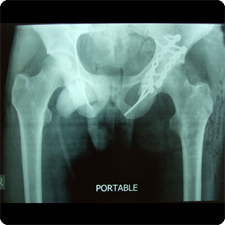

| Pre-Operation | Post-Operation |

![]() Shattered fracture of the proximal femur (clickimage for enlarge view) | ![]() Fracture fixed with plate and screws (clickimage for enlarge view) |